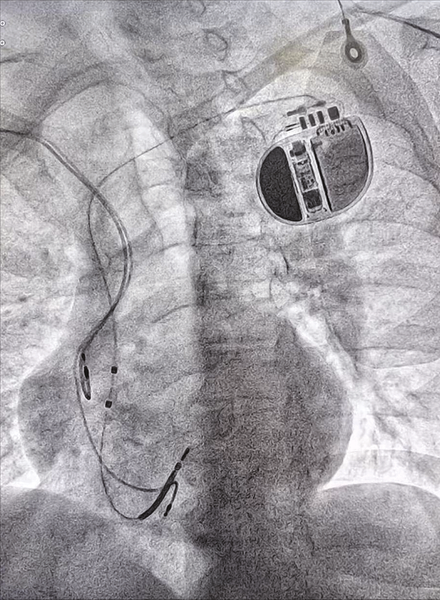

但鉴于张大爷仍有反复心律失常发作史,并且曾经出现过阿-斯综合征发作的惊险状况,为了防止悲剧再次上演,团队决定为他植入一枚ICD(植入式心脏复律除颤器)。

ICD是一种能够实时监测心律并及时进行电击复律的先进医疗设备,堪称是守护心脏节律的“保镖”,可在危急时刻挽救患者生命。

在经过详细的术前准备、排除各项禁忌后,吴向军主任医师团队凭借精湛的技术,成功为张大爷完成了 ICD植入术。手术过程非常顺利,为张大爷13年的心病,筑起了一道坚固防线。